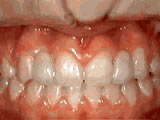

Spacing of teeth

spacing of teeth beforeBefore

spacing of teeth afterAfter

Patient was bothered by the spaces between his teeth. Braces closed the spaces and gave him an ideal bite in 24 months. Special glued-in retainers help keep the spaces closed.